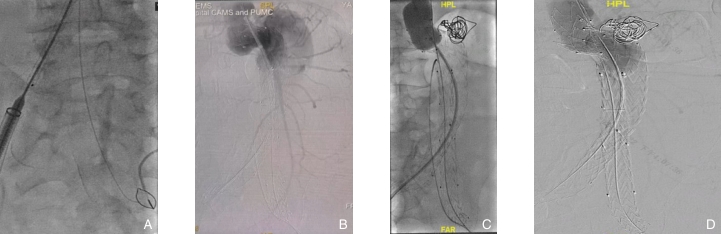

图3 术中造影资料 A:术中经肱动脉途径将导丝送入左髂动脉,抓捕器抓出导丝,建立左侧髂腿通路;B:支架植入后造影可见I型内漏;C:经预留的椎动脉导管在瘤颈周边置入可控弹簧圈+生物蛋白胶,CODA球囊充分扩张;D:再次造影,Ⅰ型内漏明显减少Fig.3 Intraoperative angiography findings A: Guidewire advanced into the left iliac artery via the brachial artery and retrieved using a snare to establish the left iliac limb pathway; B: Angiography after stent deployment showing type I endoleak; C: Controlled coil embolization with biologic glue applied around the aneurysm neck via the reserved vertebral artery catheter, followed by full expansion with a CODA balloon; D: Repeat angiography showing a significant reduction in the type I endoleak